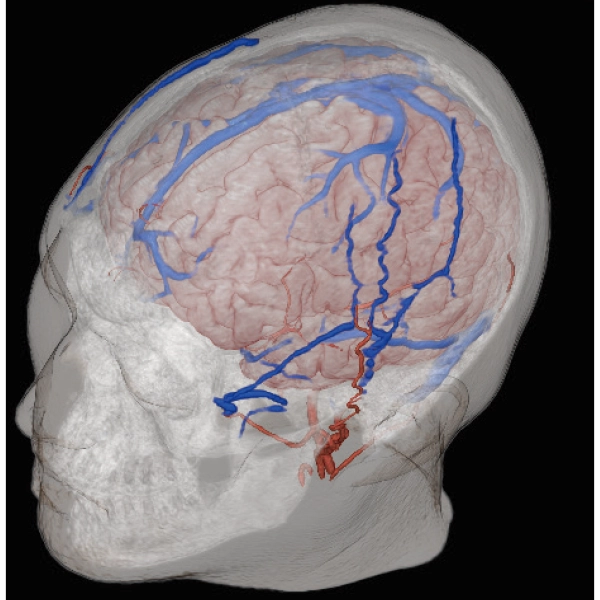

3DTOF MRA (MIP), 1:26

3DTOF MRA RADAR (MIP)

3D MRCPA (MIP)

Lower extremity

non-contrast MRA (MIP)